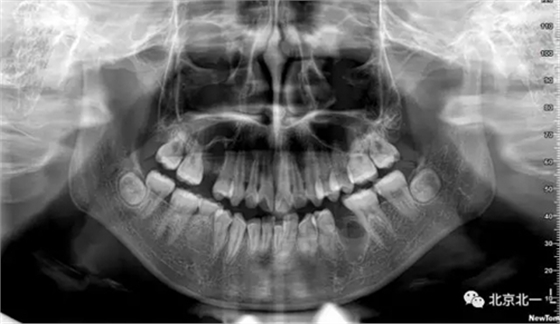

圖一:拔牙前影像片(CBCT)